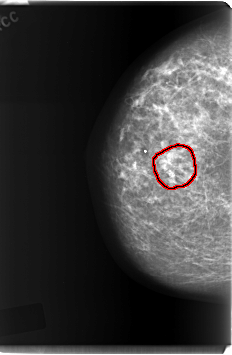

FILE: C_0213_1.RIGHT_CC.OVERLAY

TOTAL_ABNORMALITIES 1

ABNORMALITY 1

LESION_TYPE CALCIFICATION TYPE PLEOMORPHIC DISTRIBUTION CLUSTERED

ASSESSMENT 5

SUBTLETY 5

PATHOLOGY MALIGNANT

TOTAL_OUTLINES 1

BOUNDARY